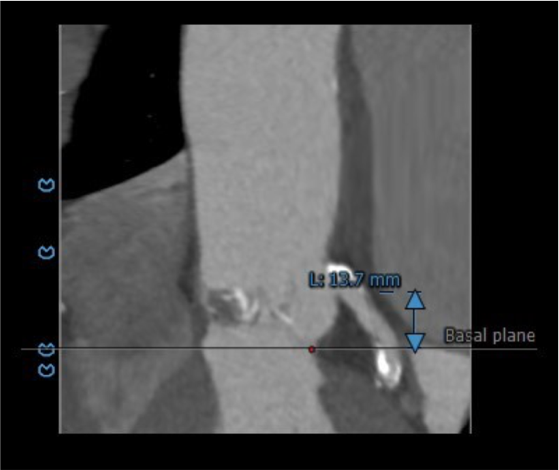

主动脉根部评估:

患者为79岁男性,术前超声心动图提示三叶式主动脉瓣重度狭窄伴中度关闭不全、瓣叶明显钙化增厚、峰值流速 3.63m/s、平均跨瓣压差 33mmHg、有效瓣口面积 0.9cm²;左心扩大,室间隔增厚;二尖瓣中轻度反流、三尖瓣轻度反流;LVEDd:59mm,LVEF:53%。